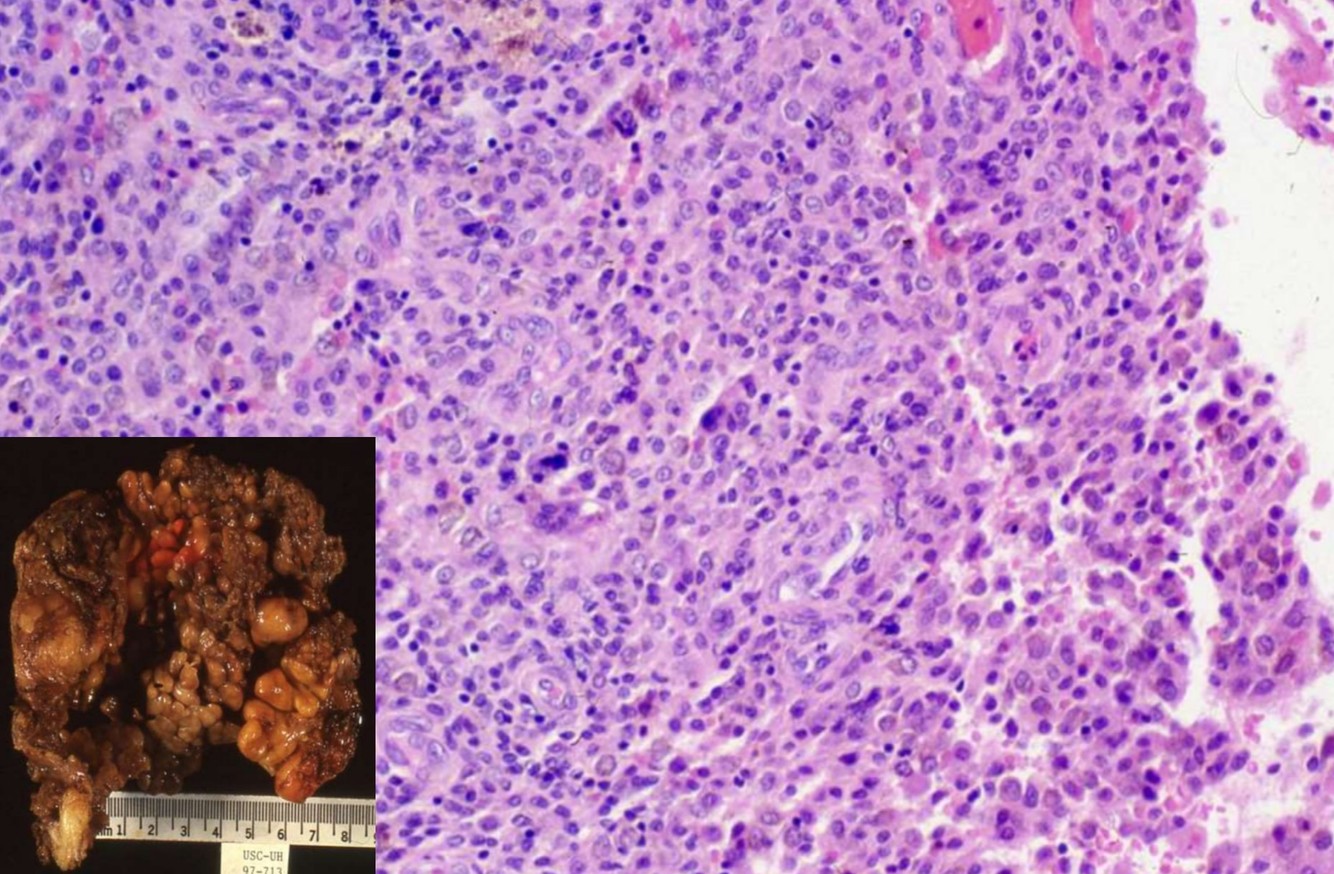

ALVEOLAR SOFT PART SARCOMA

• Genetics:

• t(X;17)

• Chromosomen1, 5, 13, 17 abnormalitys

• Clinical:

• Deep soft tissue of oral cavity, pharynx, mediastinum, thigh/leg

• Usually young females

• Highly malignant, although clinical course is slow/indolent

• Metastases up to 30 years later to veins, lungs, other

• Lung metastases may be presenting feature

• Gross:

• Well circumscribed, large, gray-yellow, hemorrhage, necrosis

• 2-14 cm

• Histology:

• Well defined nests of cells separated by fibrous stroma

• Alveolar pattern if cells discohesive

• Composed of large polygonal cells with granular eosinophilic cytoplasm, vesicular nuclei, prominent nucleoli

• Vascular invasion common; also characteristic rod-shaped crystalloids

• No/rare mitotic figures, minimal pleomorphism

• Positive: TFE3, PAS+ diastase resistant needle-like structures, MyoD1 (cytoplasmic only)

• Prognostic impact:

• Size, presence of 17q25 abnormality, AJCC stage, age

• Diff DX: metastatic renal cell ca, paraganglioma